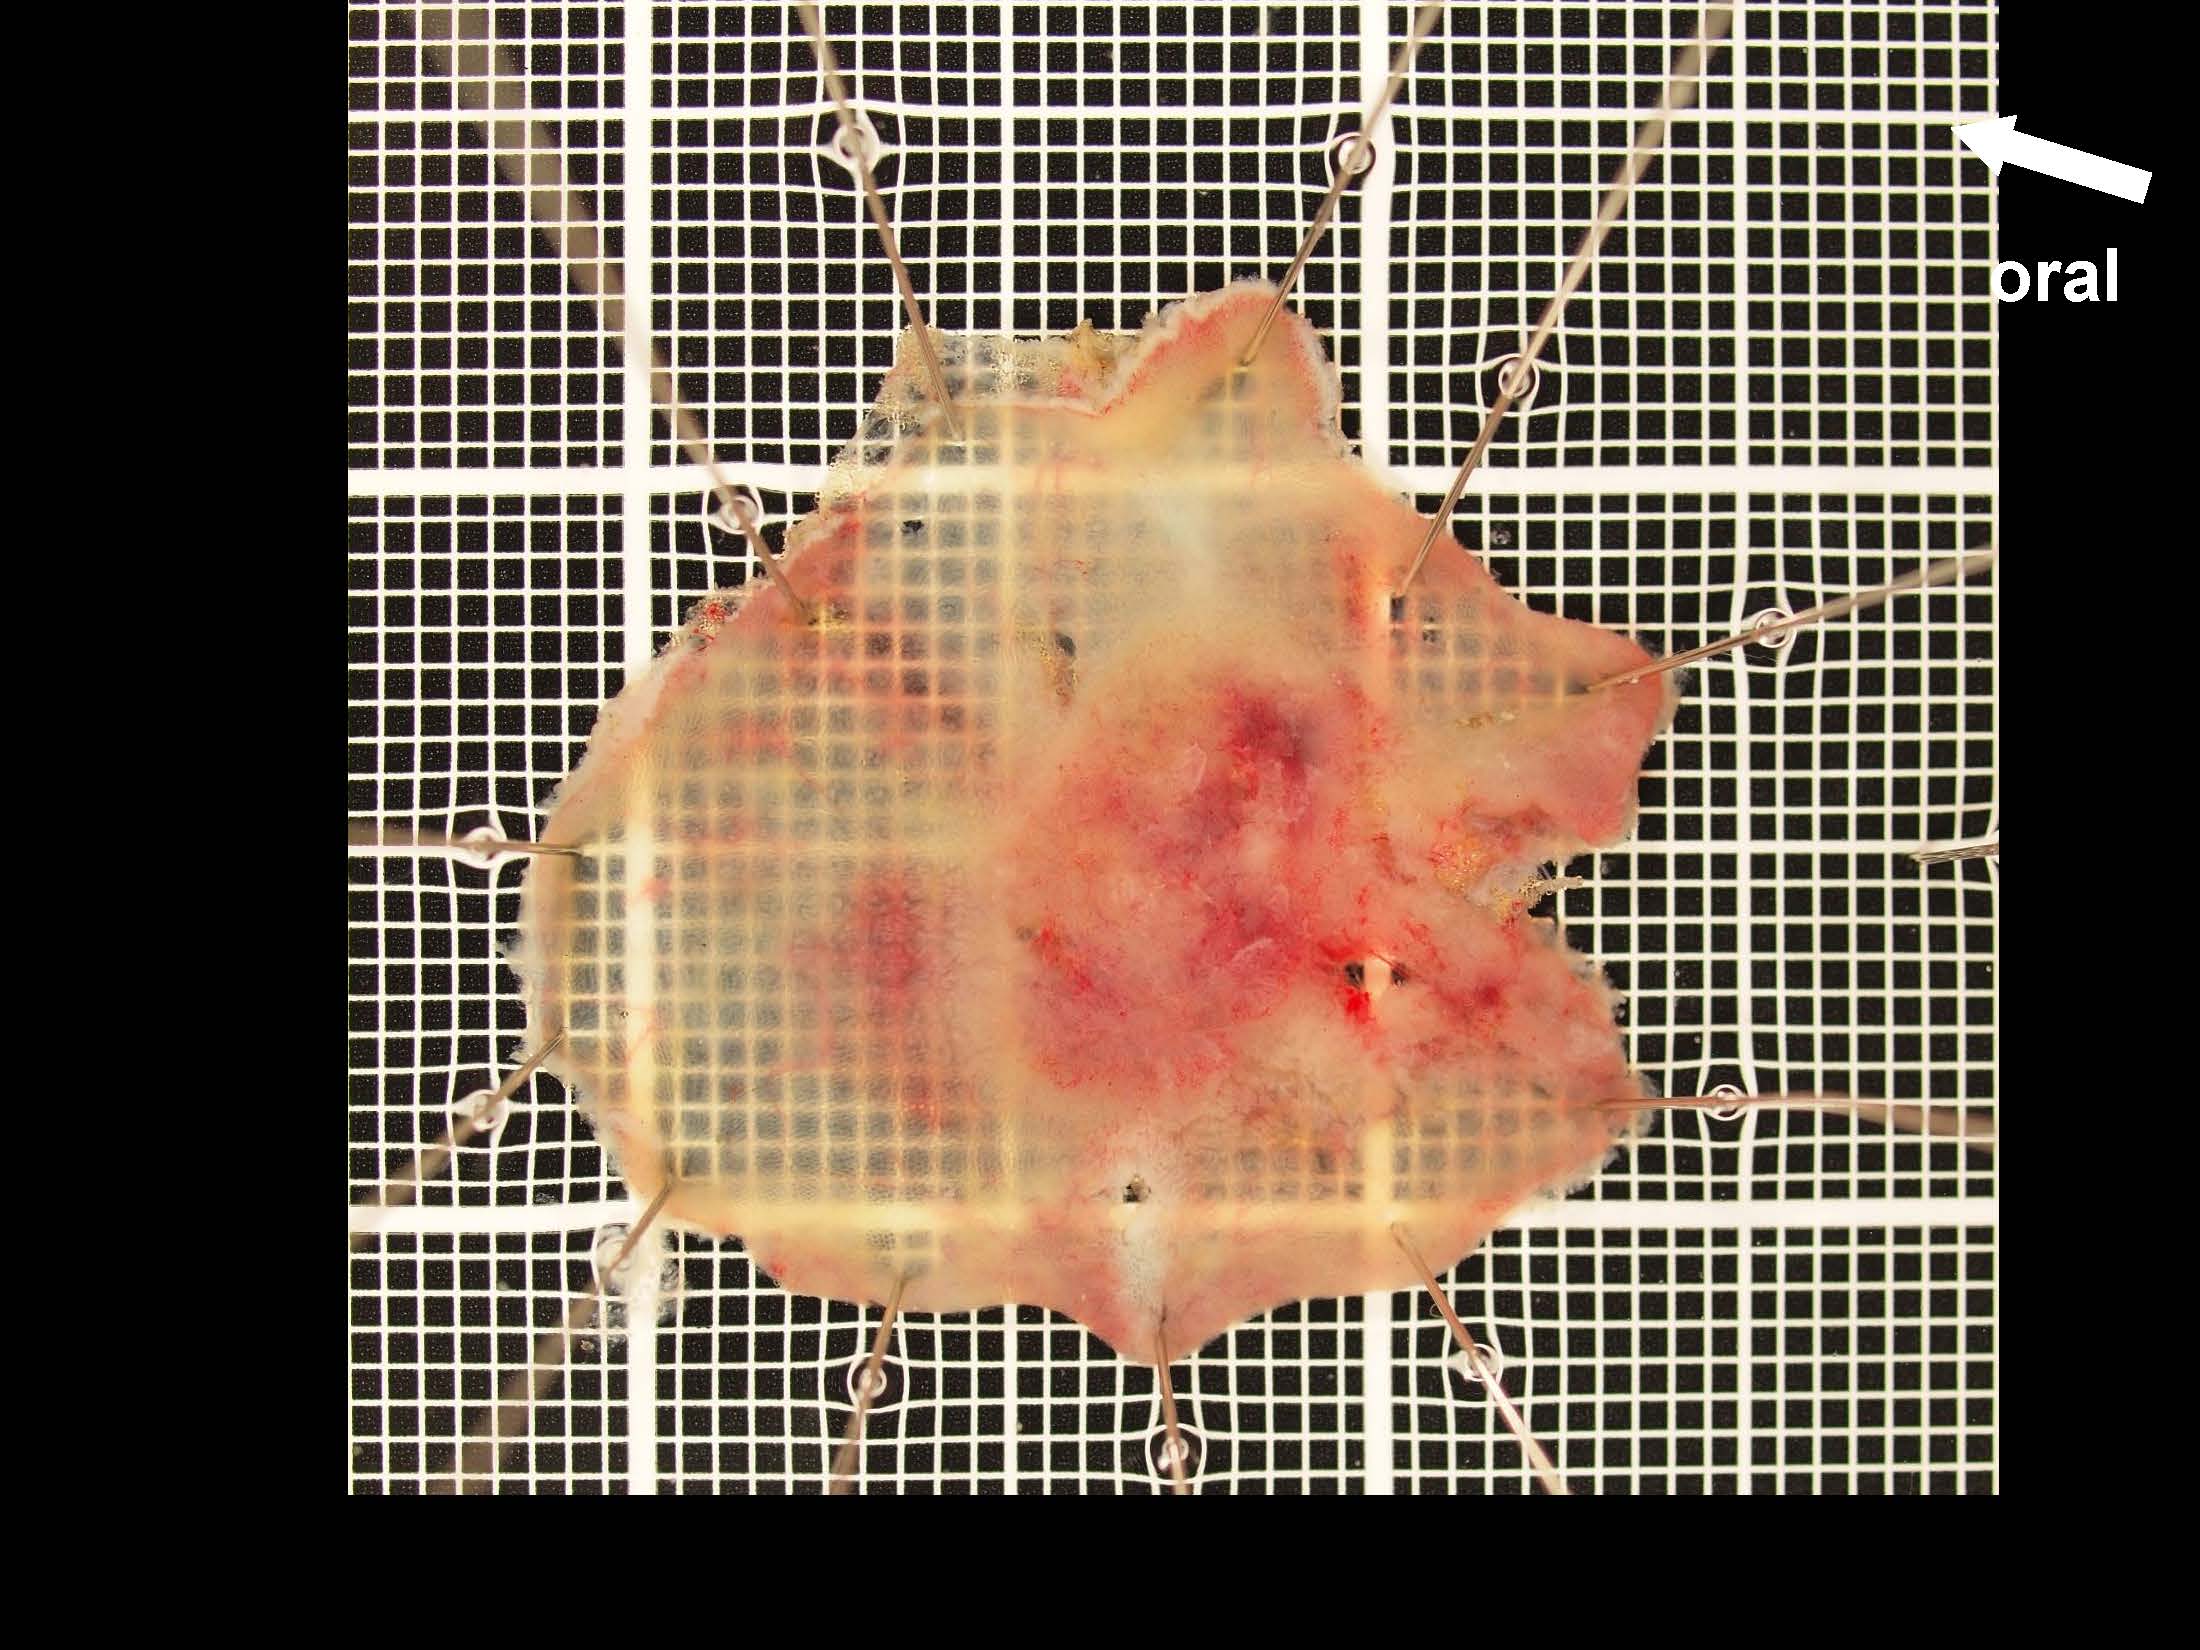

消化管Mapping~大腸~ 2021.10.27

消化管Mapping

消化管Mapping~大腸~

消化器内科

内視鏡検査・治療